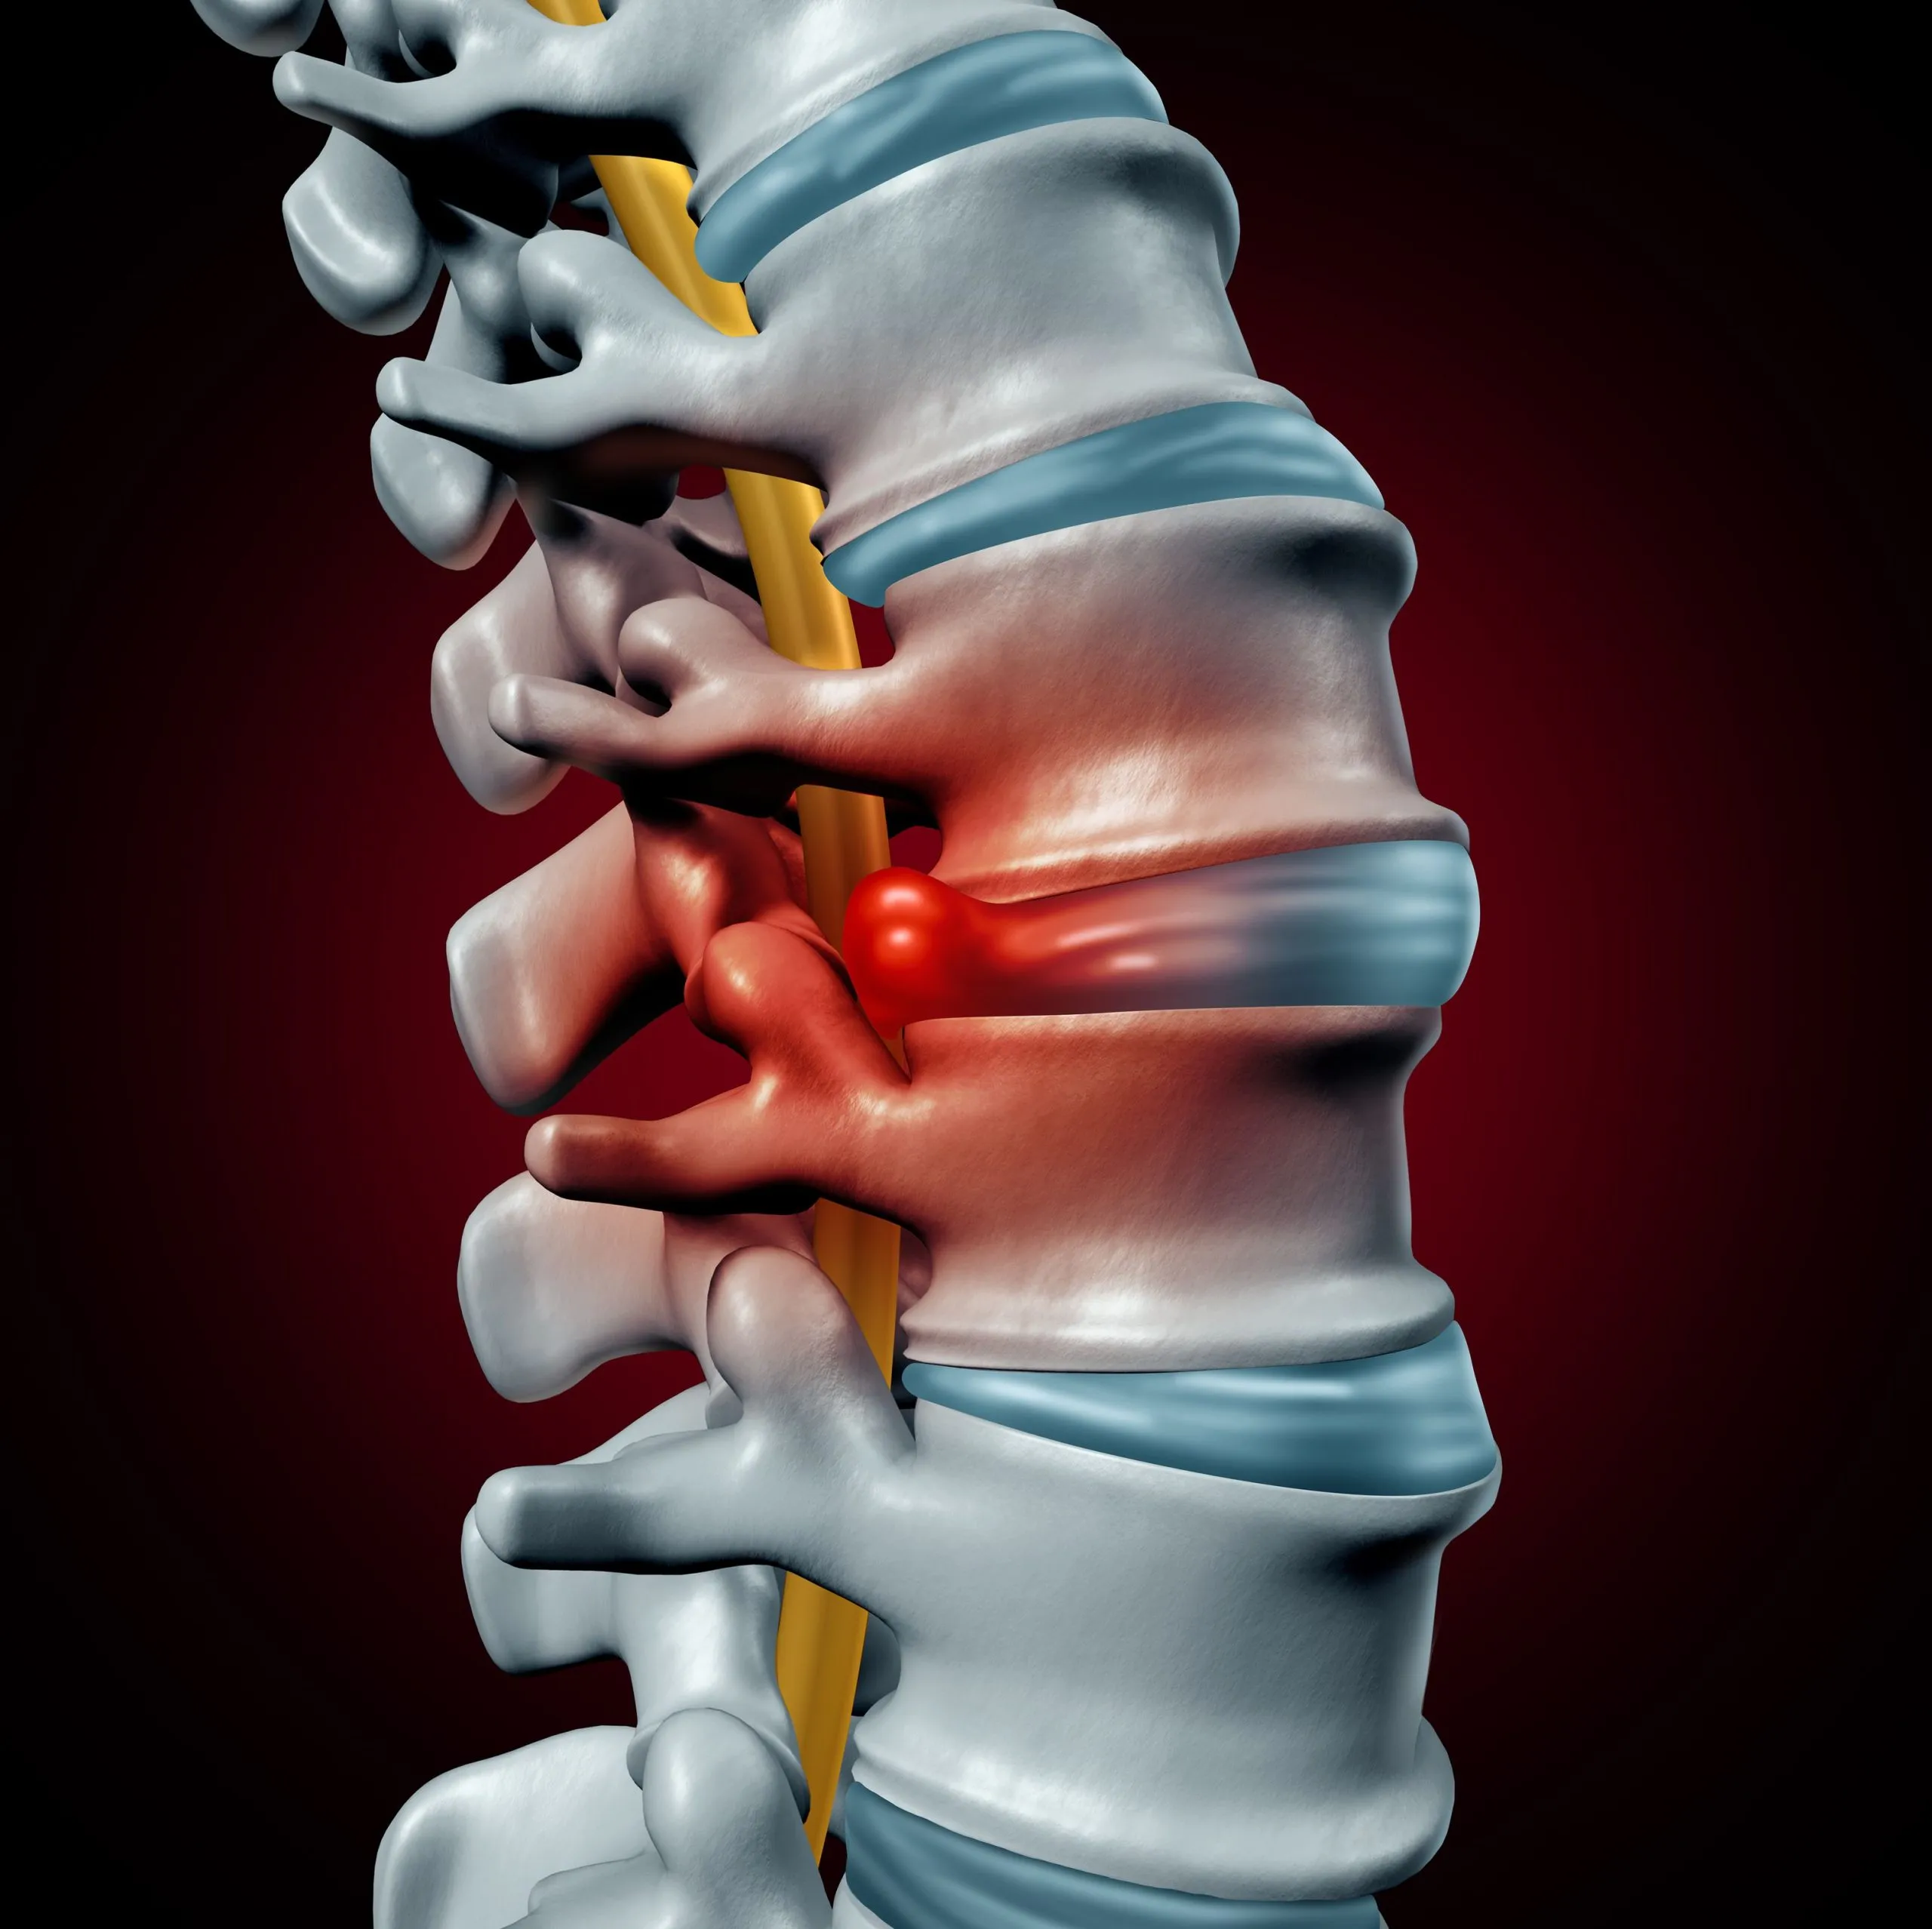

A herniated disc occurs when the soft inner core (nucleus pulposus) of a spinal disc pushes through a tear in the outer ring (annulus fibrosus), causing inflammation.

Herniated discs are most common in the lumbar spine, with symptoms starting as localized back pain that, if progressed to nerve compression, can radiate down the legs. This is known as sciatica.

Herniation triggers inflammation that irritates the nerves in the outer annulus fibrosus. This leads to back pain. It is a common misconception that a pinched nerve is the primary cause of pain.

That said, herniated discs may affect nerve function by irritating or compressing the spinal nerve roots that exit the spinal column. This can cause a variety of symptoms, including pain, numbness, tingling, or weakness in the areas served by the affected nerve.